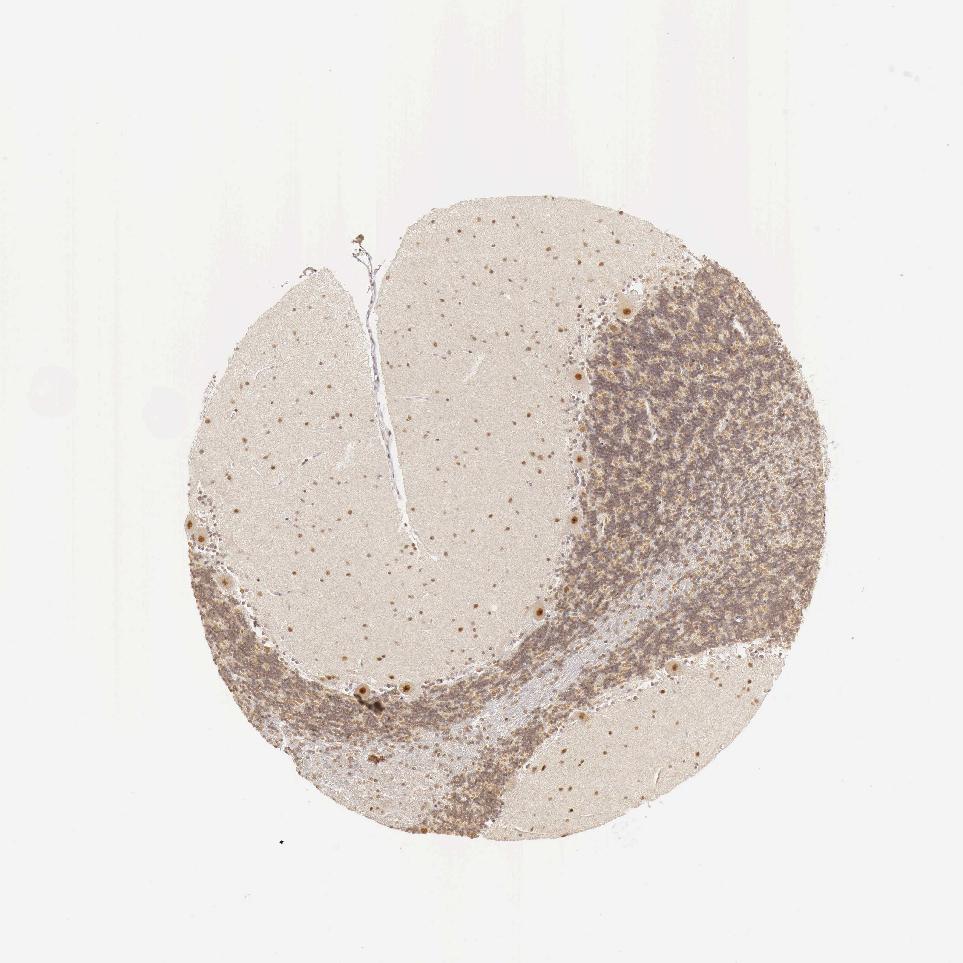

CEREBELLUM - Antibody stainingi

Antibody staining in the annotated cell types in the current human tissue is reported as not detected, low, medium, or high, based on conventional immunohistochemistry profiling in selected tissues. This score is based on the combination of the staining intensity and fraction of stained cells.

Each image is clickable and will lead to virtual microscopy that enables deeper exploration of all samples and also displays staining intensity scores, fraction scores and subcellular localization as well as patient and tissue information for each sample.

Antibody HPA000287Antibody HPA001894

Purkinje cells HighHigh

Cells in granular layer MediumHigh

Cells in molecular layer MediumHigh